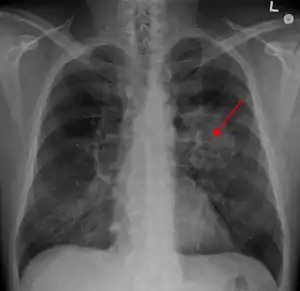

A chest X-ray showing a tumor in the lung (marked by arrow) | |

Performing a chest radiograph is one of the first investigative steps if a person reports symptoms that may be suggestive of lung cancer. This may reveal an obvious mass, the widening of the mediastinum (suggestive of spread to lymph nodes there), atelectasis (lung collapse), consolidation (pneumonia), or pleural effusion.[15] CT imaging of the chest may reveal a spiculated mass which is highly suggestive of lung cancer, and is also used to provide more information about the type and extent of disease. Bronchoscopic or CT-guided biopsy is often used to sample the tumor for histopathology.[13]

Lung cancer often appears as a solitary pulmonary nodule on a chest radiograph. However, the differential diagnosis is wide. Many other diseases can also give this appearance, including metastatic cancer, hamartomas, and infectious granulomas caused by tuberculosis, histoplasmosis or coccidioidomycosis.[65] Lung cancer can also be an incidental finding, as a solitary pulmonary nodule on a chest radiograph or CT scan done for an unrelated reason.[66] The definitive diagnosis of lung cancer is based on the histological examination of the suspicious tissue[2] in the context of the clinical and radiological features.[12]